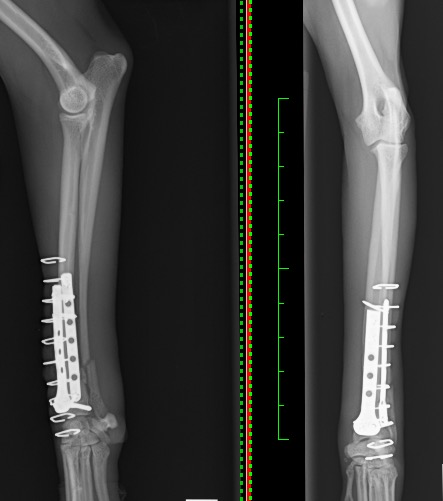

正面に1.5mmのT字プレート、外側面に1.3mmのストレートプレートを設置するダブルプレート法による整復を行いました。

左が側面像、右が正面像になります。

整復後 Lateral/AP